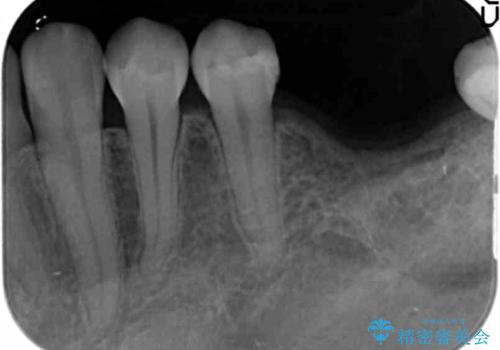

- 虫歯を放置し他院で抜歯後、入れ歯を提案されインプラント治療を希望され来院されました。

CT画像より骨の量は少なくそのままではインプラントの埋入が難しい状態です。

骨造成を行い安定したインプラントの環境を整える治療を計画します。